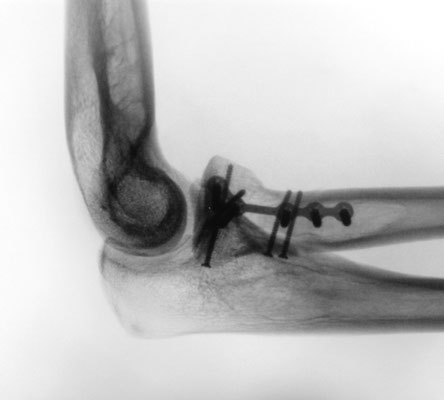

Ellenbogennaher Ellenbruch (Olecranonfraktur)

Der Ellenhaken (Olecranon) stellt den knöchernen Teil dar, über den die Kraft des Trizepsmuskels in den Unterarm geleitet wird und somit die aktive Streckung des Ellenbogens gegen Widerstand ermöglicht wird. Durch den Zug der Trizepssehne wird das kleine Knochenfragment weggezogen. Die Kraftübertragung des Muskels auf den Unterarm ist abgehängt. Insofern ergibt sich die Erfordernis, das Knochenteil und damit auch die Sehne des Trizeps wieder am Unterarm zu befestigen. Zusätzlich muss auch die Kongruenz des Gelenkes wieder hergestellt werden. Je nach dem, ob es sich um einen einfachen oder komplizierten Knochenbruch handelt, wird eine sog. Zuggurtungsosteosynthese mit zwei Drähten und einer Achterschlinge (Abb. 6a-b) oder eine Stabilisierung mit einer Platte durchgeführt.